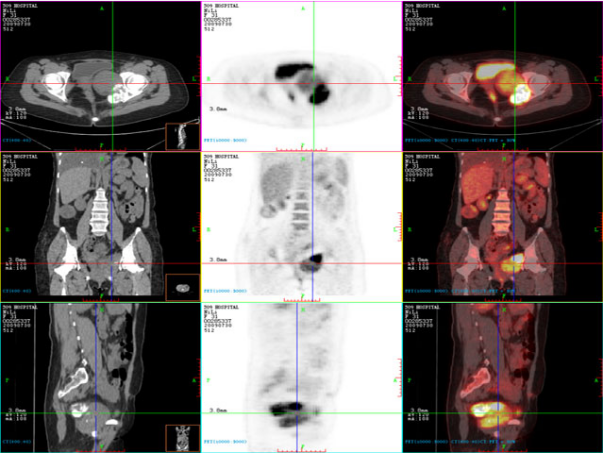

提升医疗技术,满足患者就医需求。医学影像党支部所辖科室积极开新技术,为科室的不断发展注入强劲动力。影像科积极开展了磁共振脑灌注加权成像(PWI)、磁共振波谱成像技术(MRS)、乳腺MRI及动态增强技术、发射型计算机断层扫描仪(ECT)、臂丛、腰丛磁共振成像技术、CT脑灌注成像技术(CTP)、冠状动脉检查技术(CTA)、正电子发射断层-X线计算机断层组合系统(PET-CT)等新技术,超声科为了充分满临床的需求开展了术中经食道超声心动图检查、新生儿颅脑超声检查及超声引下穿刺活检等。

(正电子发射断层-X线计算机断层组合系统(PET-CT)) (冠状动脉检查技术(CTA))